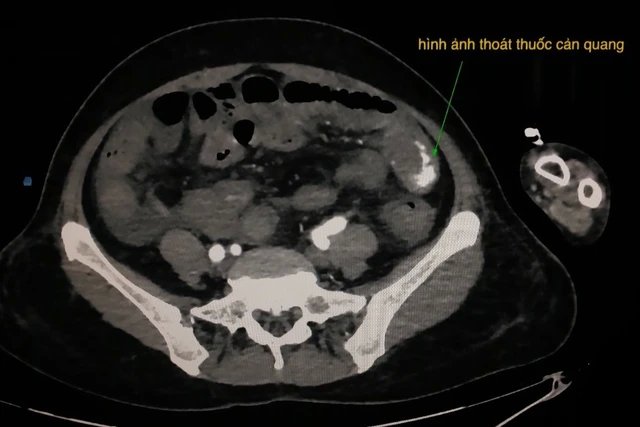

Hình thoát thuốc cản quang trên phim chụp cắt lớp vi tính bụng của bệnh nhân.

Kết quả kiếm tra ghi nhận bệnh nhân bị sốc mất máu nặng, chỉ số huyết học ở mức báo động: huyết sắc tố 4.0 g/dl (bình thường: 12.5 – 16 g/dl). Khi bệnh nhân di chuyển được bác sĩ tiến hành chụp cắt lớp vi tính bụng có cản quang trước kiểm tra tình trạng thoát mạch. Kết quả ghi nhận hình ảnh thoát mạch thuốc cản quang trong thành quai ruột non hông trái, không thấy u bướu hay polyp.